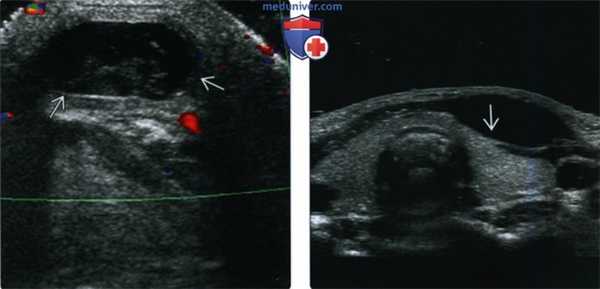

(Слева) На поперечной сонограмме в подкожных тканях визуализируется гипоэхогенное объемное образование с ровными краями, расположенное парамедианно справа, спереди от подподъязычных мышц. Образование было оперативно удалено, подтвердилась КЩЯП.

(Справа) На поперечной сонограмме у ребенка с подозрением на кисту щитоязычного протока в области предполагаемой локализации в нижних отделах шеи визуализируется щитовидная железа, имеющая нормальный вид (состоящая из двух долей). У всех пациентов, обследуемых на предмет КЩЯП, важно документально отразить наличие щитовидной железы в ожидаемом месте и отсутствие патологических изменений с ее стороны.

4. УЗИ при кисте щитоязычного протока:

• Анэхогенное или гипоэхогенное срединное образование шеи:

о ± внутренние эхогенные включения (±кровоизлияния или инфекция):

о Наличие эхогенных включений внутри кисты не соотносится с гистологическими признаками кровоизлияния или инфекции

• При исследовании нижних отделов шеи необходимо убедиться в отсутствии патологических изменений щитовидной железы, наличии обеих долей

(Слева) УЗИ в поперечной плоскости у ребенка с вновь появившимся объемным образованием передних отделов шеи слева: визуализируется патологический гетерогенный очаг без признаков кровотока при цветовой допплерографии, но с выраженными эхогенными включениями, наличие которых позволяет заподозрить дермоид или рак в КЩЯП. При патоморфологическом исследовании подтвердилась киста, не осложненная кровоизлиянием, инфекцией, без признаков наличия злокачественной опухоли.

(Справа) УЗИ в поперечной плоскости у восьмилетнего ребенка: визуализируется типичная подподъязычная КЩЯП в виде анэхогенного объемного образования, расположенного парамедианно и обусловливающего легкое сдавливание левой доли щитовидной железы, в остальном выглядящей нормальной.